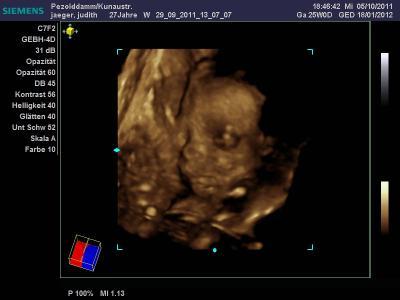

Hallo ihr lieben Kugeln! Ich hoffe, es geht euch allen gut und ihr und die Zwerge seid gesund und munter! Bevor ich morgen in die 32.SSW kugele, war heute noch das 3.Screening und hier kommt der Bericht: Nach den üblichen Kleinkrams (Urin, Blutdruck, Blutabnahme, wiegen) gings ans CTG, zuerst Herztöne suchen. Baby hat erstmal die Arzthelferin schön getreten, wollte wohl nicht, dass man auf der Wohnung rumdrückt. Haben die Töne dann gefunden und das CTG angeschlossen, wir mussten aber den Sensor halten und drauf drücken. Zwischendurch waren die Töne immer mal wieder weg, es hat sich wohl in die andere Ecke verkrümelt und ordentlich protestiert und geboxt und getreten. Die Arzthelferin musste sogar zwischendurch neu angelegen. Dann gings zum Ultraschall: Köpfchen liegt unten, Körper rechts vom Bauchnabel (ich merke in letzter Zeit dort was Hartes, was sich gegen mich stemmt, das ist dann wohl der Rücken). Wir konnten super die Rippen, Wirbelsäule und das Herzchen sehen und auch das Seitenprofil des Gesichtes gut erkennen. Die Ärztin hat dann versucht, auf 3D umzuschalten, aber Baby hatte die Hand vorm Gesicht und uns den Finger gezeigt. Ist also leider nix geworden mit nem schönen Foto. Aber wir konnten sehen, dass unser Nachwuchs noch immer eine Schnute zieht (das angehängte Bild ist vom 3D-US Anfang Oktober, aber es sieht quasi noch genauso aus...) Kopfumfang beträgt 28,05 cm, Brustkorbumfang 25,78 cm. Oberschenkelknochen ist 5,93 cm lang und das errechnete Gewicht beträgt 1732g. Alles zeitgerecht, der ET (18.1.) wird auch beibehalten. Die Ärztin ist zufrieden und auf meine Frage, ob das ok ist, dass ich bisher nur 4 Kilo plus hab, meinte sie, ich solle mir da keine Gedanken machen sondern froh drüber sein, es sei alles in Ordnung. Sprich das Gewicht, was ich jetzt mehr drauf hab, ist ausschließlich Baby und Fruchtwasser. Mal sehen, was die nächsten Wochen noch so kommt. Soviel erstmal für heute von mir Euch weiterhin alles Gute und viele Grüße, Ju

Bild zu Bericht vom 3.Screening - Forum für Januar - Mamis